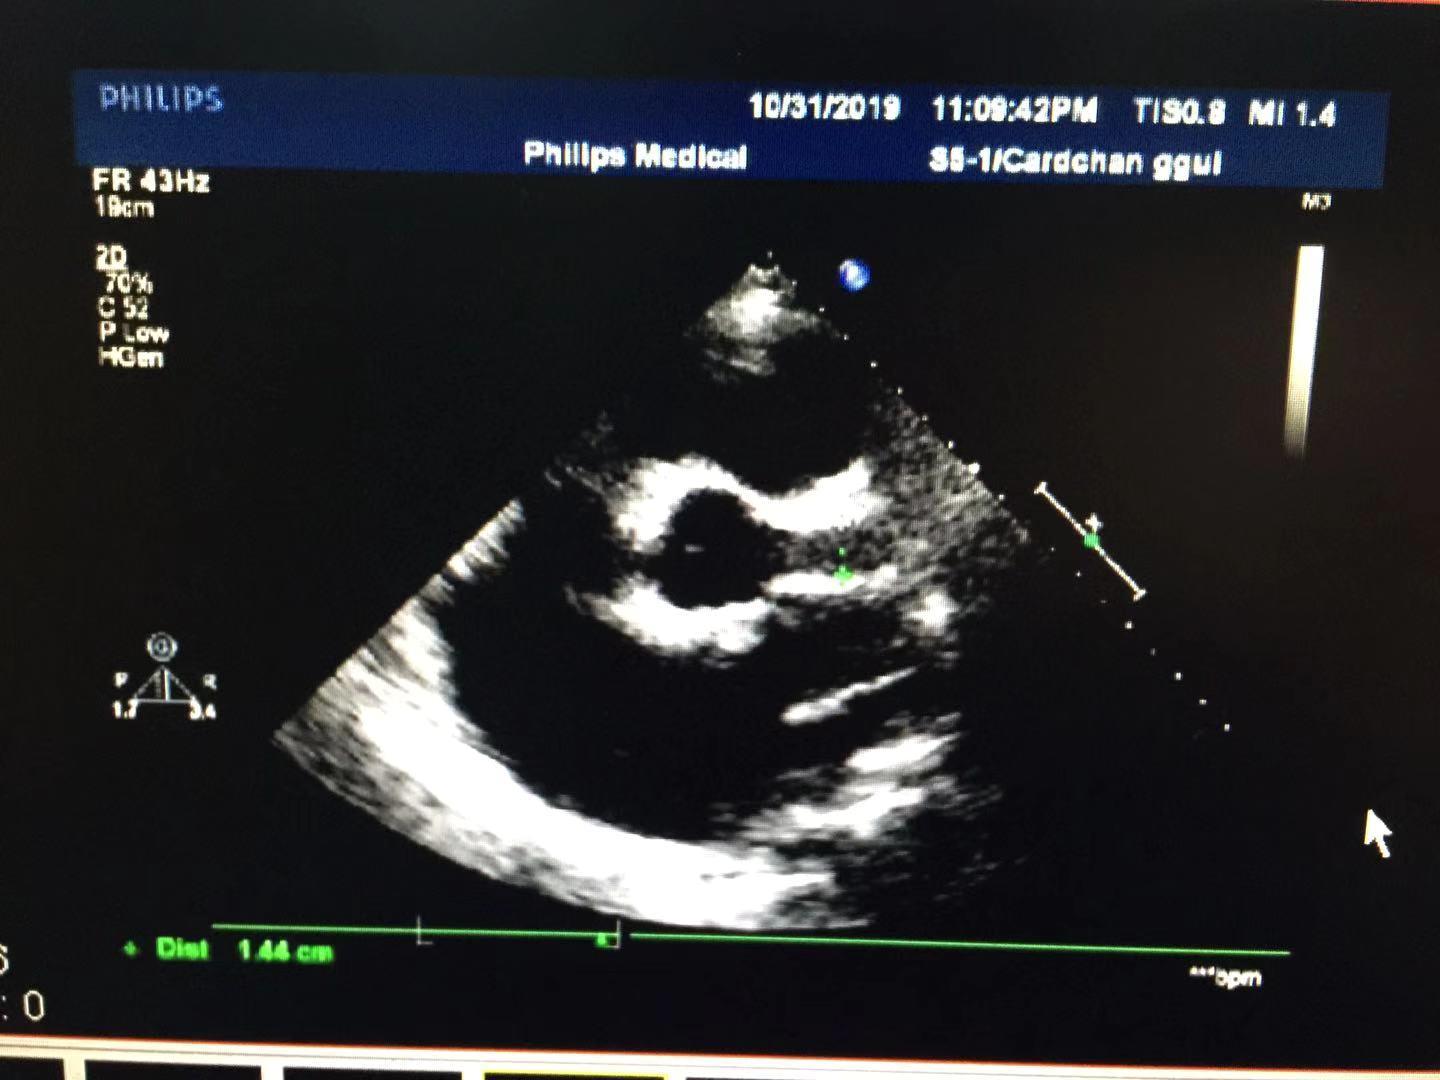

超声所见:全心大,肺动脉主干内径增宽。左冠状动脉迂曲增宽,可视长度明显增加,开口处内径约14mm,增宽的左冠状动脉沿左房越过房间隔开口于右心房,瘘口直径约8mm。房、室间隔连续完整,左室侧后壁运动减弱,余室壁运动尚可。各瓣膜形态正常,二尖瓣、三尖瓣、主动脉瓣开启可,关闭欠佳。心包腔内探及液性暗区,左室后壁深约17mm,右室之前深约13mm。CDFI:于右房内可见以舒张期异常血流信号。二尖瓣、三尖瓣口可见收缩期返流信号。主动脉瓣口可见舒张期返流信号。

(左冠状动脉增宽)